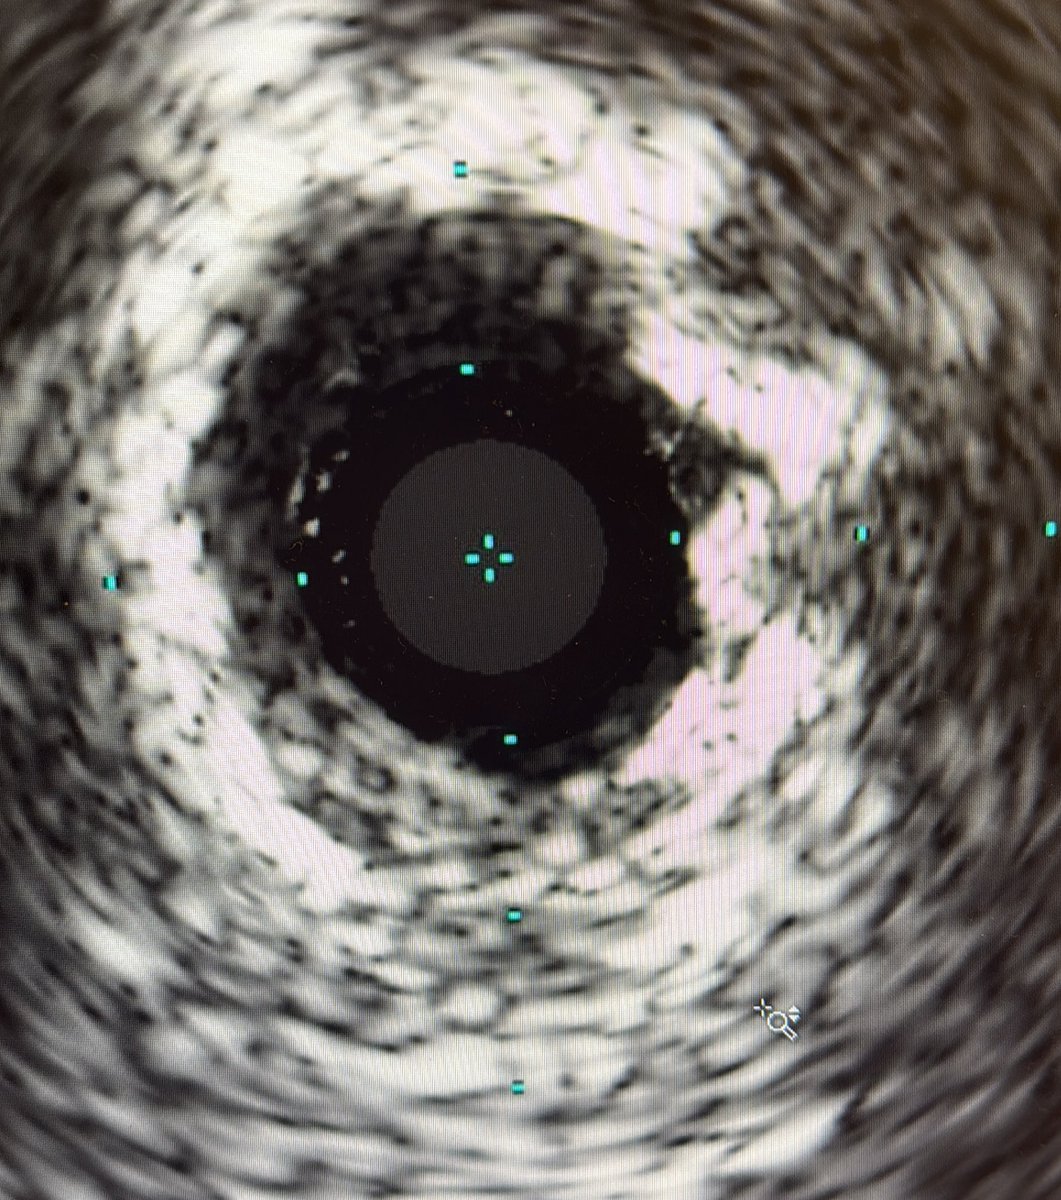

How to handle this? DCB available, FYI. @realarainmd @ShariqShamimMD @jl35wilsonMD @AuroraCVFellows @DanielJohnsrud @evandrofilhobr @RSohnMD @DrWhyWho @DrBIqbal @drAliyor @mornei2011 @SyedYNaqvi1

19

12

67